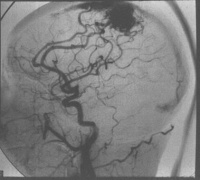

脑动脉造影[编辑 | 编辑源代码]

脑动静脉畸形有以下典型表现:①显示畸形血管。这是特征表现,呈一团管径相仿相互纠缠的迂曲扩张血管。畸形血管团的范围可小如指甲,大如手掌,多见大脑半球皮质.②异常粗大的供养动脉和引流静脉伴局部循环加快。此为局部血流短路的表现。③血流分流现象:造影剂随血流经畸形血管的短路大量流入静脉,因此,血管畸形部分因血流量增加而显影十分清楚。④血肿的表现:血管破裂出血致脑内血肿,血肿的主要表现为局部占位征象,一股脑部动静脉畸形无血肿时,脑血管不出现占位征象,脑血管不移位。

5.脑血管造影:最可靠、最重要的诊断方法,动脉期可见血管团、供血动脉及早期显现的引流静脉。

4、脑血管造影是本病最可靠和主要的诊断方法,并能行血管内介入治疗。

1、由于有多发的可能,术前应作全脑血管造影或双侧颈动脉造影,或按畸形血管部位推测,加作椎动脉造影。典型的脑动静脉畸形包括供应动脉、畸形灶及引流静脉三部分。通过造影应查清供应动脉来源及引流静脉走向,畸形灶的部位及范围,有无血肿等合并症,以及病人有无它处畸形。才能制订出完善的手术计划,也是手术成功的关键。